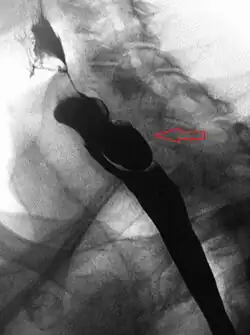

AP X-ray of a Zenker's diverticulum